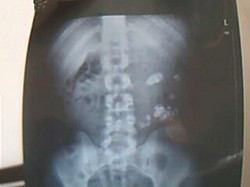

肾结石B超图